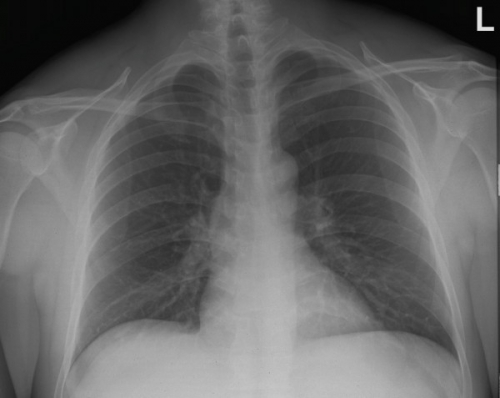

Tool to train medical student's eyes as to what a normal chest x-ray looks like, with over 500 consecutive normal images.